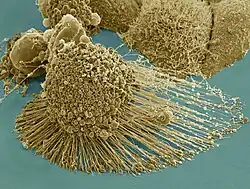

Apoptose und Nekrose sind normalerweise leicht zu unterscheiden. Die Apoptose beginnt mit einem Schrumpfen der Zelle, und die DNA wird durch Endonukleasen in definierte Stücke zerlegt, Die DNA-Fragmente sind durch die TUNEL-Methode im Chromatin nachweisbar oder erscheinen in einem Gel nach Elektrophorese als DNA-Leiter.

Der Ablauf der Apoptose lässt sich lichtmikroskopisch verfolgen. Zuerst löst sich die betreffende Zelle aus dem Gewebsverband. Im weiteren Verlauf färbt sich die Zelle mehr und mehr eosinophil an und wird zunehmend kleiner. Außerdem bilden sich an der Zellmembran sichtbare Bläschen. Der Zellkern wird kleiner, sein Chromatin dichter gepackt. Er kann im Verlauf der Apoptose auch in mehrere Teile zerfallen. Am Ende des Vorgangs bleibt ein homogen eosinophiles Apoptosekörperchen. Dieses wird dann durch Phagozytose abgebaut. Der programmierte Zelltod löst dabei keine Entzündungsreaktion aus.[7]

Letztlich schnürt die Zelle nach und nach kleine Vesikel ab, die wiederum durch spezialisierte „Fresszellen“ (Phagozyten) aufgenommen werden. Im Gegensatz zur Nekrose bleibt hierbei die Zellmembran intakt.

Die Clearance apoptotischer Zellen ist der letzte Schritt bei der Entfernung alter, beschädigter, infizierter und gefährlicher Zellen in den Geweben multizellulärer Organismen. Der Prozess schont dabei das umgebende Gewebe so gut wie möglich. Apoptotische Zellen durchlaufen enorme morphologische Veränderungen.[20] Dazu gehören Kontraktion, Membran-Blebbing (Bläschenbildung) und eine apoptotische Zellform. Das Membran-Blebbing trägt aktiv zur Erkennung und Aufnahme toter Zellkörper und zur Induktion autoreaktiver Antikörper bei. Unter Blebbing versteht man die Bildung von Membranbläschen auf der Oberfläche der apoptotischen Zelle. Diese Bläschen sind von Lipiden der Zytoplasmamembran umgeben und enthalten Teile des Inhaltes der sterbenden Zelle. Blebs sind ballonförmige Bläschen, die sich durch Auswölbung der Plasmamembran auf der Zelloberfläche bilden. Sie entstehen in einem dynamischen Prozess während der Apoptose auf der gesamten Zelloberfläche. Der Bildung von Blebs geht ein erhöhter hydrostatischer Druck in der Zelle voraus, der durch die Actomyosin-gesteuerte Kontraktion der Zelle verursacht ist. Neugeformte Blebs enthalten noch kein Aktin oder andere zytoskeletale Proteine. Später polymerisieren dann schnell zytoskeletale Vorläuferproteine, was zur Rückbildung der Blebs führt. Der Vorgang der Bleb-Bildung und -Rückbildung wiederholt sich während des Prozesses der Apoptose. In der späten Apoptose können individuelle Blebs mit Zellorganellen und kondensiertem Chromatin gefüllt werden. Abgeschnürte Chromatin-gefüllte Blebs können als Viromimetika zur Induktion anti-nukleärer Antikörper beitragen.[21] Oberflächenblebs und abgegebene membranumhüllte Mikropartikel werden meist von Makrophagen im näheren Umfeld aufgenommen.